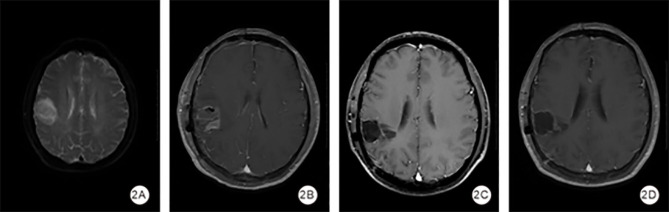

背景:本研究旨在评价表观扩散系数(ADC)值、水肿程度和全身免疫炎症指数(SII)对高级别胶质瘤(HGG)术后早期复发的预测价值。方法:本回顾性研究分析2018年5月至2023年6月在湖南省第二人民医院接受手术治疗的HGG患者的数据。患者分为早期复发组(术后6个月内)和非早期复发组。采用受试者工作特征(ROC)曲线建立基于ADC、水肿程度和SII的HGG早期复发预测模型。结果:共纳入68例HGG患者,其中早期复发20例(29.5%)。早期复发组与非早期复发组患者年龄、肿瘤大小、水肿程度、病理分级差异均有统计学意义(P < 0.05)。肿瘤ADC的ROC曲线下面积(AUC)为0.623 (95% CI: 0.461 ~ 0.786),敏感性为0.500,特异性为0.854;水肿程度为0.652 (95% CI: 0.517-0.787),敏感性为0.900,特异性为0.458;SII为0.781 (95% CI: 0.663-0.900),敏感性为0.750,特异性为0.729。联合模型的AUC为0.823 (95% CI: 0.715-0.931),敏感性为0.800,特异性为0.708。结论:综合评价肿瘤ADC值、SII、水肿程度对HGG早期复发具有预测价值。

Background: This study aimed to evaluate the predictive value of apparent diffusion coefficient (ADC) values, degree of edema and the systemic immune-inflammation index (SII) for early postoperative recurrence in high-grade gliomas (HGG).

Methods: This retrospective study analyzed data from patients with HGG who underwent surgery at the Second People's Hospital of Hunan Province between May 2018 and June 2023. Patients were divided into early recurrence (within six months post-surgery) and non-early recurrence groups. Receiver operating characteristic (ROC) curves were used to develop predictive models for early recurrence of HGG based on ADC, degree of edema and SII.

Results: A total of 68 patients with HGG were included, of whom 20 (29.5%) had early recurrence. Significant differences were observed between the early recurrence and non-early recurrence groups in age, tumor size, degree of edema, and Pathologic grading (all P < 0.05). The area under the ROC curve (AUC) for tumor ADC was 0.623 (95% CI: 0.461-0.786) with a sensitivity of 0.500 and a specificity of 0.854; for degree of edema, it was 0.652 (95% CI: 0.517-0.787) with a sensitivity of 0.900 and a specificity of 0.458; and for SII, it was 0.781 (95% CI: 0.663-0.900) with a sensitivity of 0.750 and a specificity of 0.729. The combined model yielded an AUC of 0.823 (95% CI: 0.715-0.931) with a sensitivity of 0.800 and a specificity of 0.708.

Conclusion: The combined evaluation of tumor ADC values, SII, and the degree of edema offers predictive value for early recurrence in HGG.